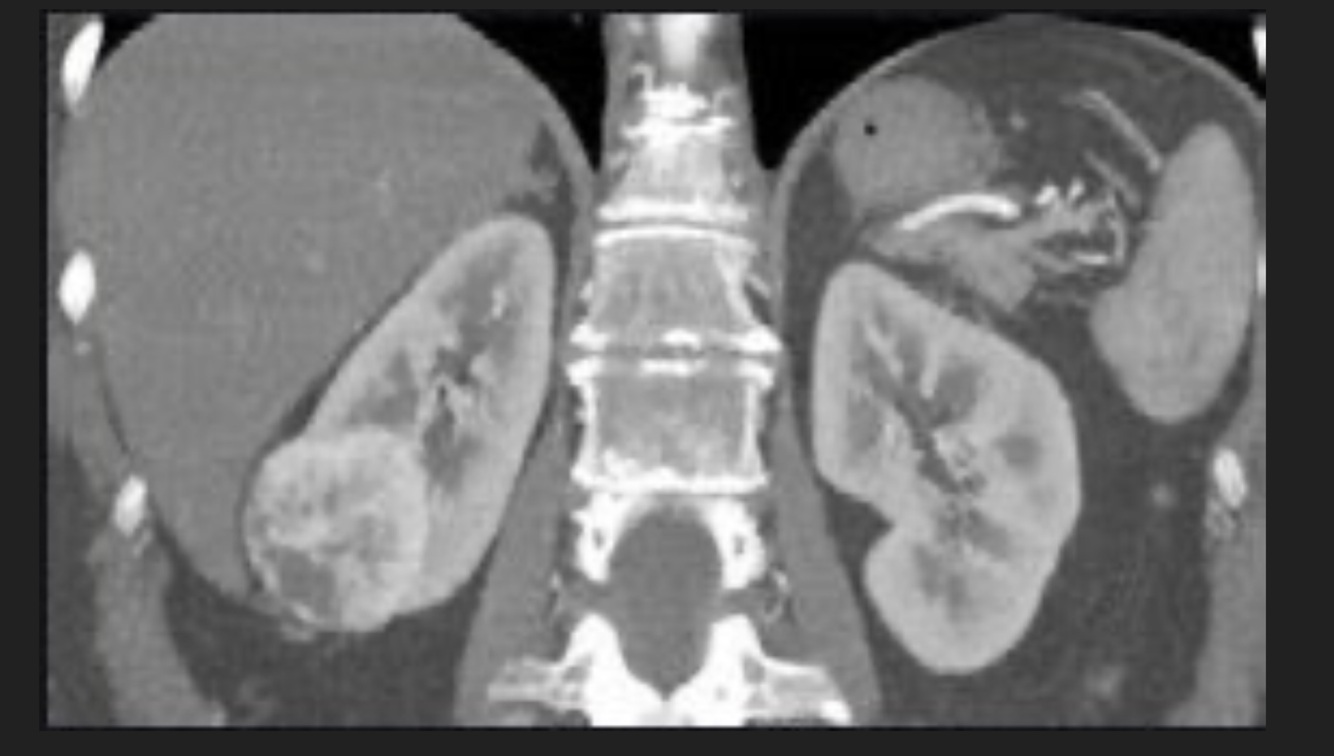

Q

-Tabaquismo +

-Astenia

-Adinamia

-Hiporexia

-Baja de 12 kg en cuatro meses

-Hematuria silenciosa

A

Cáncer renal